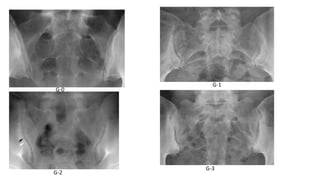

Grading of Sacroiliitis: New York Criteria

• Grade 0: normal

• Grade 1: suspicious -some blurring of the joint margins

• Grade 2: Minimal abnormality with small areas of erosions or

sclerosis without alteration in the joint width

• Grade 3: Unequivocal abnormality - moderate or advanced sacroiliitis

consisting of erosion, sclerosis, widening, narrowing, and/or partial

joint fusion (ankylosis)

• Grade 4: Complete ankylosis

G-0

G-1

G-3

G-2